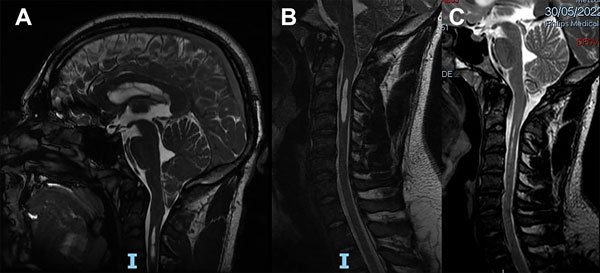

Caso 5: Control evolutivo postoperatorio

Un varón de 22 años de edad, deportista de contacto profesional, consultó por presentar una MCI con SM. Sólo presentaba apneas de sueño confirmadas por una polisomnografía. La RM mostraba un descenso amigdalino de 17 mm y una SM ubicada entre C3 y C4 (Figura 7A-B). Teniendo en cuenta su profesión y los síntomas se indicó cirugía. Se le realizó una descompresión cráneo cervical y duraplastia con periostio. La evolución postoperatoria transcurrió sin complicaciones. A los 5 meses de la cirugía se le realizó una RM en contraste de fase en donde se observó que la SM no se había reducido y las velocidades del LCR eran de 10 cm/seg. Siguió bajo control y a los 16 meses de la cirugía se observó la desaparición de la SM (Figura 7C) y en la nueva RM en contraste de fase la normalización de las velocidades del LCR (2,3 cm/seg.). Fue dado de alta definitivamente pudiendo reasumir su actividad deportiva.

Figura 7: Caso 5. A: RM de cerebro en plano sagital ponderada en T2 que muestra el descenso amigdalino de 17 mm de configuración de bordes agudos y el extremo proximal de una siringomielia cervical. B: RM de columna cervical en plano sagital ponderada en T2 que muestra una siringomielia entre C3 y C4. C: RM de columna cervical en plano sagital ponderada en T2 que muestra la resolución de la siringomielia.